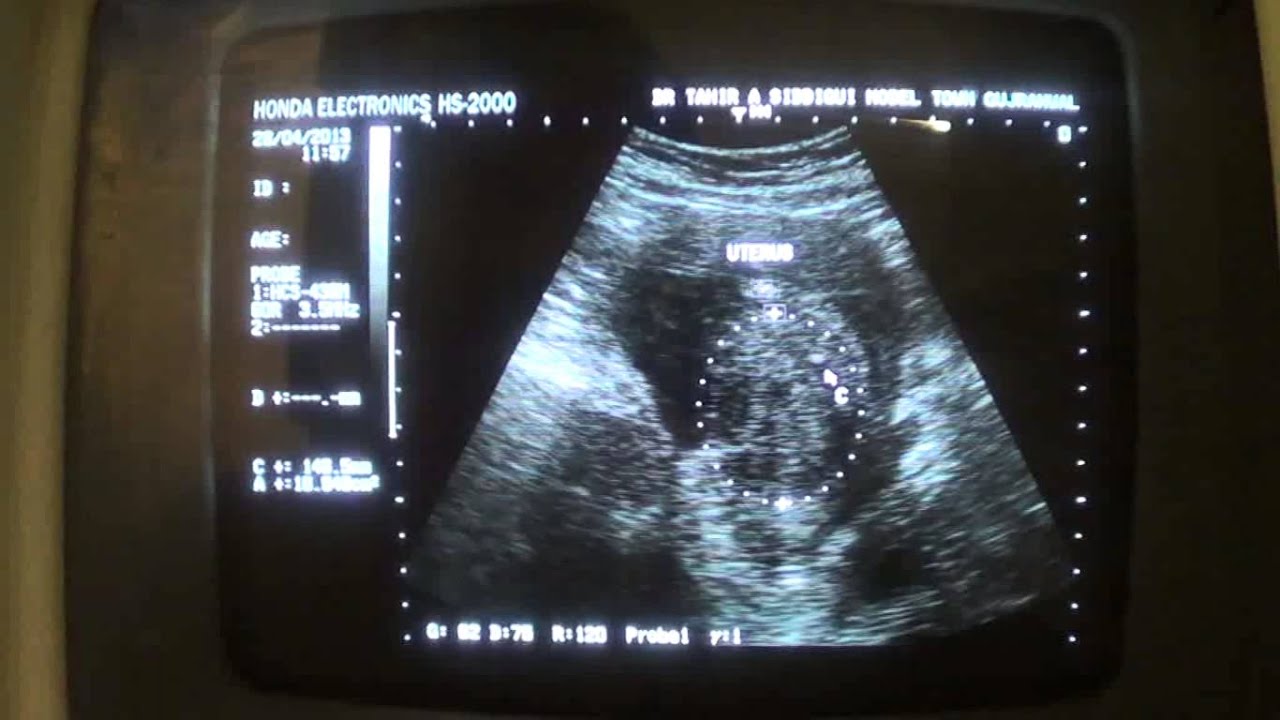

From www.youtube.com

UTERINE FIBROID in postmenopausal age YouTube Postmenopausal Bleeding Uterine Fibroids  Treatment may not be necessary if you have fibroids but do not. However, a person should seek medical advice if they have bothersome.  there can be several causes of postmenopausal bleeding. The most common causes are:   after menopause, fibroids usually shrink, and symptoms improve.  rapid or unexpected growth of fibroids after the menopause.   while it’s extremely. Postmenopausal Bleeding Uterine Fibroids.